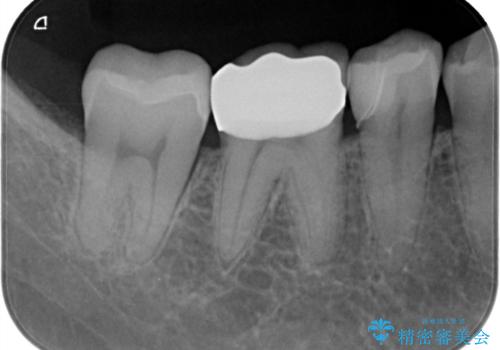

銀歯だったところは、歯質を削る量が多かったためクラウンにて治療し、前後の歯に関してはインレーにて治療を行なっております。

また、歯肉に関してもきれいに治って患者様も満足されていました。